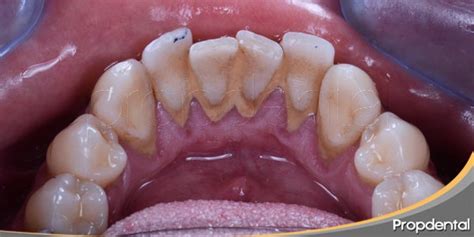

El sarro está compuesto por los restos microbianos, la acumulación de residuos de alimentos y de saliva. La mala higiene bucodental es la principal causa de su aparición. Es común que dicha calcificación del biofilm dental se acumule en el borde de las encías o en los espacios interdentales donde no llegamos con el cepillado.

El biofilm dental y los restos de alimentos se deben eliminar a diario evitando que lleguen a endurecerse. Estos restos pueden presentar una coloración que va desde un tono blanquecino, amarillento, hasta un color marrón en los casos más severos. En algunos casos, el sarro puede volverse negro debido a ciertos factores, como tener una alta concentración de hierro en la saliva. Cuanto más tiempo dejes que el sarro dental permanezca en tu boca, más bacterias se acumularán a su alrededor.